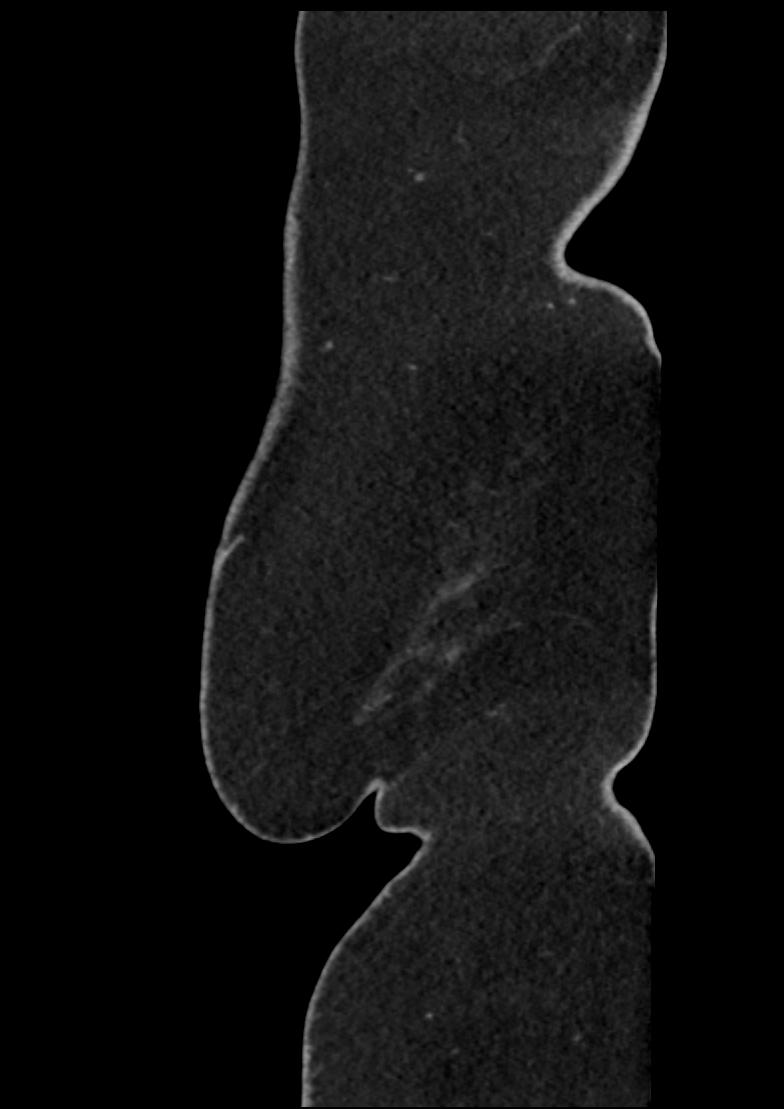

Patient: Padmakumar A. , *1988-04-24, PID: 3000069741773230809

Study Description: CT ABDOMEN

Image Series: Abdomen Sag 3mm [4]